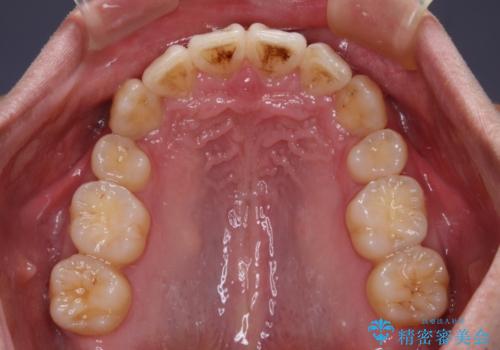

ディープバイトや奥歯の咬み合わせなど、インビザライン矯正では限界がありワイヤー装置での治療に及ばない仕上がりとなりました。

ただし、患者様としては八重歯や、それに伴う唇の閉じにくさが改善されたとのことで、納得いく状態での治療終了となりました。